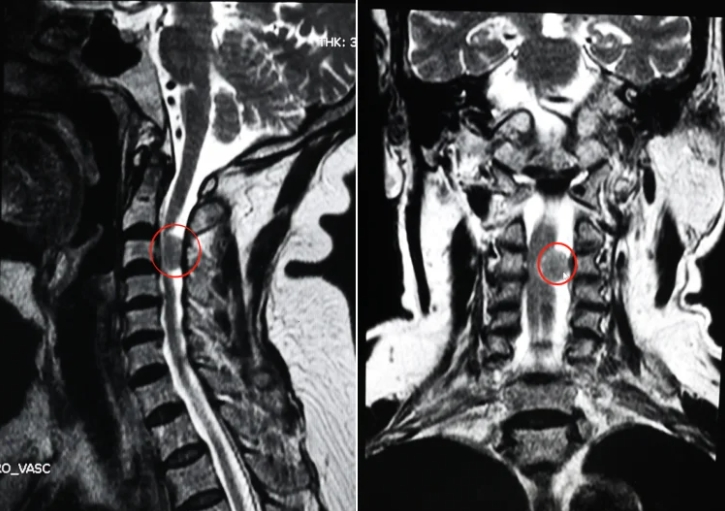

68岁王阿姨(化名),一年前因为左胳膊感觉减退,左腿走路发沉、无力,在西安市红会医院脊柱病医院腰椎病区杨俊松副主任医师处就诊。杨俊松综合评估患者情况后认为,患者颈椎管内肿瘤诊断明确,建议手术。

脊柱病医院院长郝定均和腰椎病区主任刘团江查房后指出,患者颈椎管内肿瘤诊断明确,脊髓压迫明显,建议尽快手术切除肿瘤。

术前:椎管肿瘤、脊髓受压